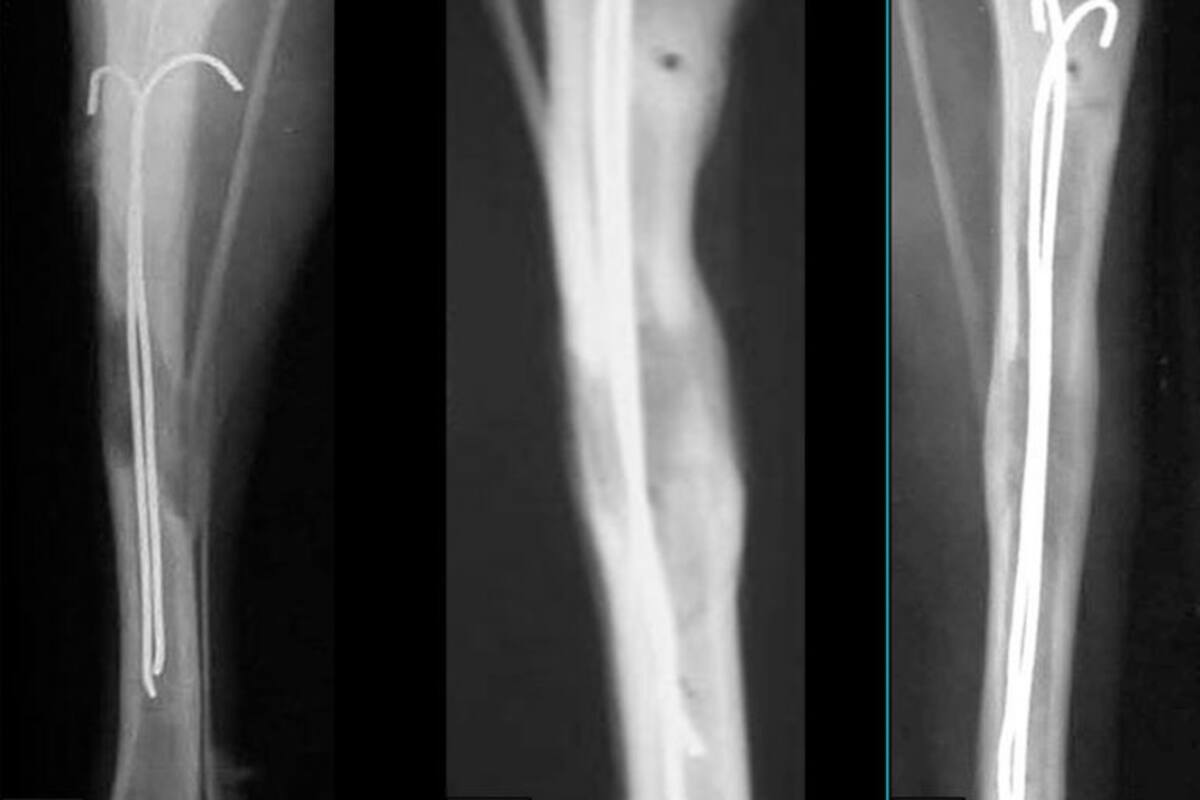

Los niños con deformaciones en los huesos se les atiende por medio del llamado método Ilizárov, que consiste en colocar un implante y varillas que se fijan en una extremidad y se interconectan.

Ahora, este procedimiento fue mejorado por investigadores de la Universidad Politécnica de Tomsk (UPT), en Rusia, quienes desarrollaron un implante con una aguja de titanio que permite aumentar la estatura.

Dicha aguja se inserta dentro del hueso y sirve como un conductor para ayudar a regenerar de manera más rápida el nuevo tejido óseo. Estos implantes están hechos como los tradicionales: de acero y compuestos BT6 (aleación de titanio con aluminio y vanadio), pero están recubiertos con otro material que se asimila al tejido óseo natural para tener una mejor tasa de supervivencia (plástico fluorocarbonado piezoeléctrico e hidroxiapatita).

La ingeniería de tejidos y la medicina regenerativa no sólo hacen posible la recuperación de tejidos, sino que ya permiten crear tejidos y órganos para sustituir a los dañados. El tipo de implante ayuda a acelerar la regeneración ósea y, como resultado, reduce el período de rehabilitación. Después de la regeneración exitosa, se retira el implante.

En 2014, un paciente entrevistado por la BBC, comentó que debido al complejo que tenía con su estatura viajó al Centro Ilizárov de traumatología restaurativa y ortopedia en Kurgan, Rusia. Después de una dolorosa operación, en la que tras fracturarle el hueso de la tibia creció 5,5 centímetros y gastó 16 mil euros entre operación y pasaje.